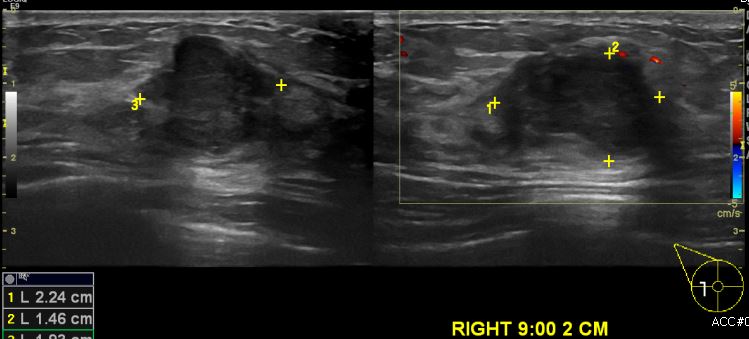

우측에 마져지는 멍울로 내원하신 40대 여성 분으로 초음파상 우측 9시 방향에서 2cm

떨어진 거리의 의심스러운 멍울 조직검사 시행하여 우측 침윤성 유관암 진단 되었습니다.